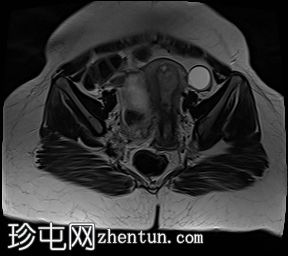

冠状位

T2加权像

4.jpg

子宫体积增大,宫底可见息肉样病变,T2加权像呈异常中高信号强度。病变可见轻度扩散受限,增强后呈均匀强化。病变与宫底交界区之间可见一界限清晰的异常高T2信号区域,可能为囊性变性。未见病变超出交界区。

在剖宫产切口远端的前壁上,可见另一处类似的较小病灶。

左侧附件囊性病变,T1加权像信号异常低,T2加权像信号异常高。无增强扫描强化。

子宫内膜息肉是子宫内膜组织的结节状突起。通常表现为T2加权像信号异常高,增强扫描后呈均匀强化。

病理检查通常显示增生期子宫内膜紊乱。